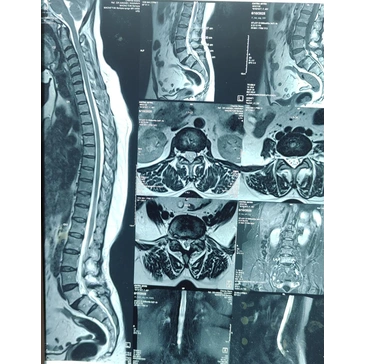

- Imaging tests to identify affected spinal area

- Diagnostic imaging to evaluate spine condition

Diagnosis typically includes clinical examination and imaging such as X-ray, MRI, or CT scan.